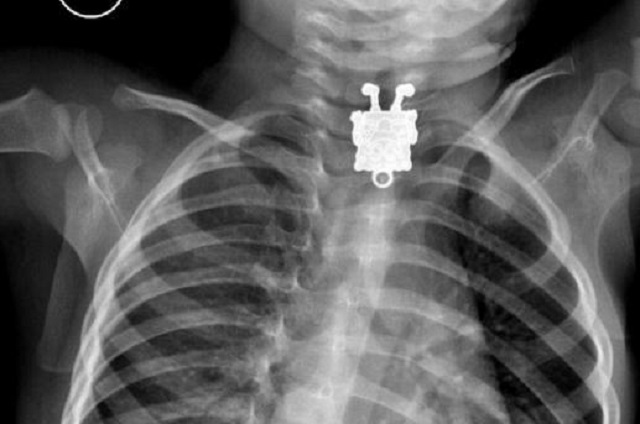

ŞOCANT! Ce au descoperit medicii în corpul unui copil de 16 ani! Radiografia a arătat totul în detaliu

Dr. Ghofran Ageely, rezident la radiologie la spitalul King Abdulaziz University Hospital din Jeddah a declarat că un copilaş de 16 luni a fost adus de urgenţă la spital de către părinţii lui care suspectau că micuţul ar fi înghiţit ceva.

Ei bine, mare le-a fost mirarea, când la radiologie s-a observat că în esofacul copilului era blocată o jucărie SpongeBob, potrivit upi.com.